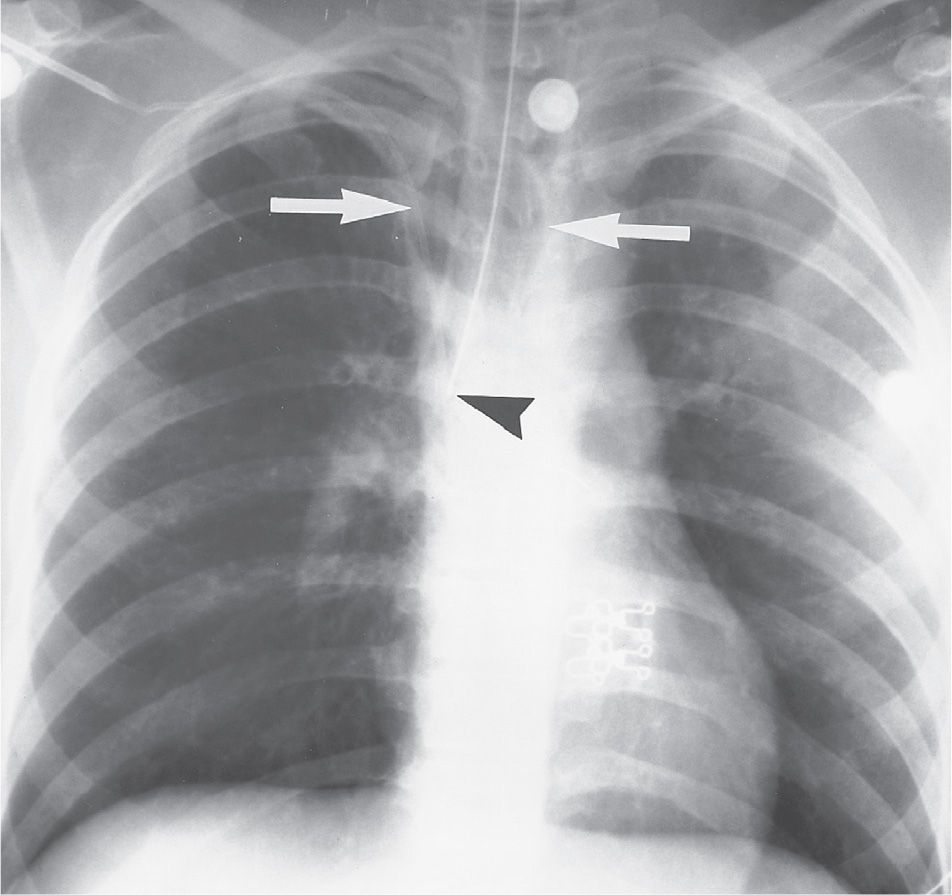

Preoperative chest Xray shows tracheal stenosis. Download Scientific